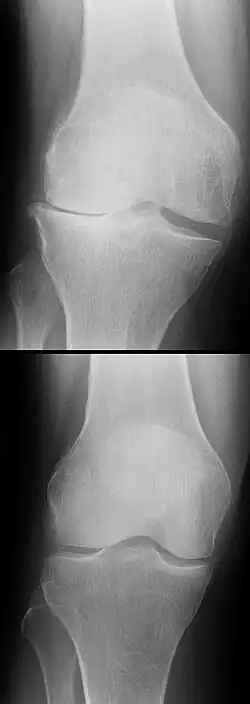

Les radios n'apportent aucune contribution immédiate au diagnostic de rupture de LC. Les deux LC sont invisibles à la radio, déchirés ou non. La seule utilité de la radio ne peut servir qu'au diagnostic des complications osseuses possibles.

L'évolution à long terme du genou être commence à bien connue dans le cas des ligamentoplasties, faisant apparaitre un haut niveau de satisfaction subjective à plus de 20 ans chez la majorité des patients, une stabilité antéro-postérieure et rotatoire normale dans 90% des cas, mais aussi une augmentation de signes d'arthrose (concernant surtout les patients ayant eu des lésions cartilagineuses ou méniscales concomitantes), ainsi qu'une altération durable de la proprioception[135],[136]. En revanche, on ne dispose pas d'études à 10 ans ou plus ni pour les protocoles récents de cicatrisation avec attelle, ni pour les toutes dernières techniques de suture chirurgicale[104].